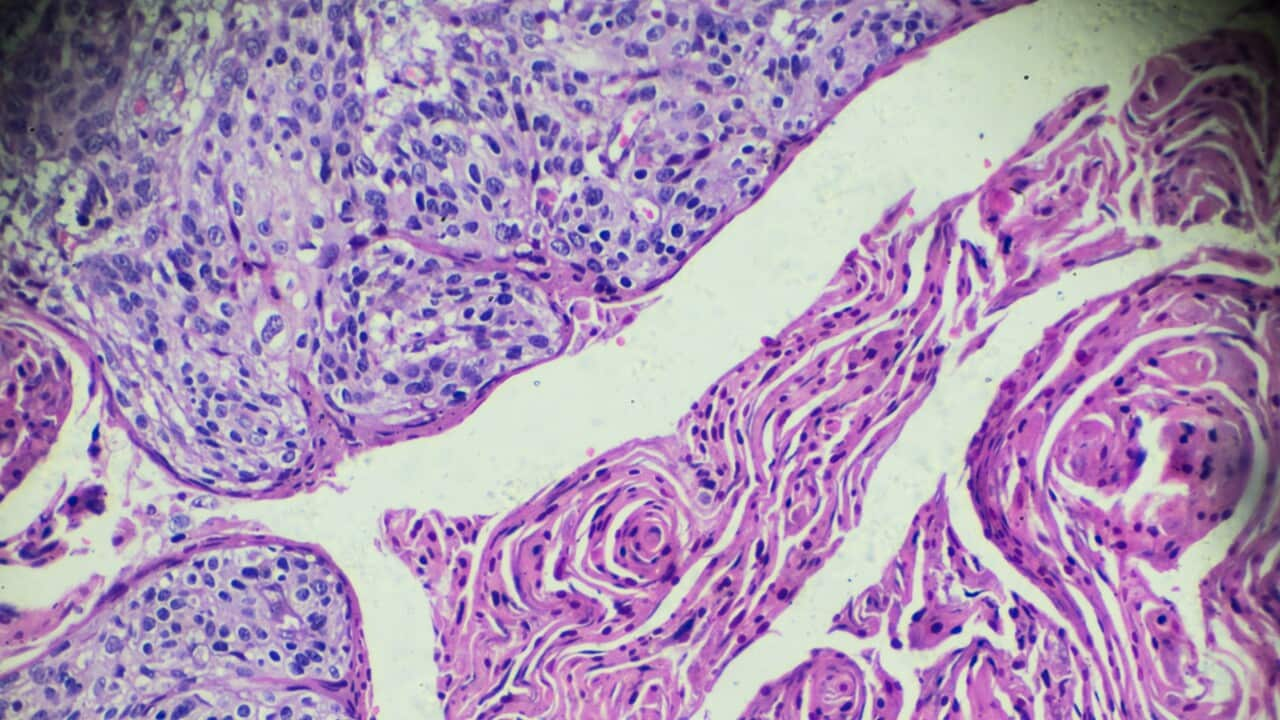

Cervical Cancer (Squamous cell carcinoma) under light microscopy zoom in different areas Source: Getty / jxfzsy

A health advocate says 1 in 3 eligible Victorians is not getting screened for cervical cancer, with the intimate procedure creating barriers to access. Cancer Council Victoria’s Kate Broun says an increasing number of people are screening from home, particularly older women and new arrivals to the country. But despite this, new data from group’s cancer registry shows that more than 200 Victorians were diagnosed with cervical cancer in 2022, with more than 1,000 cases diagnosed in the five years 2018 to 2022.